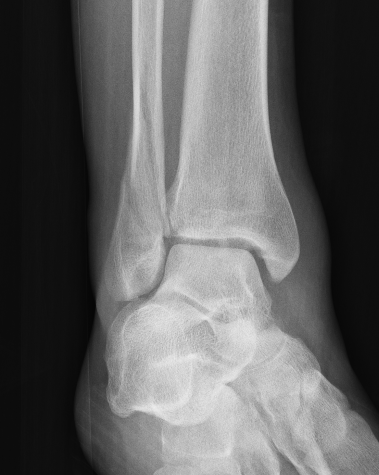

Xray

Ankle fractures with deltoid ligament rupture / Bimalleolar equivalent injury

Weber B with increased medial clear space on CT

Weber C with increased medial clear space